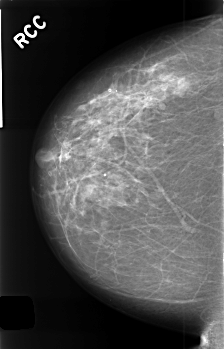

C_0408_1.RIGHT_CC

RIGHT_CC LINES 4528 PIXELS_PER_LINE 2912 BITS_PER_PIXEL 12 RESOLUTION 50 NON_OVERLAY